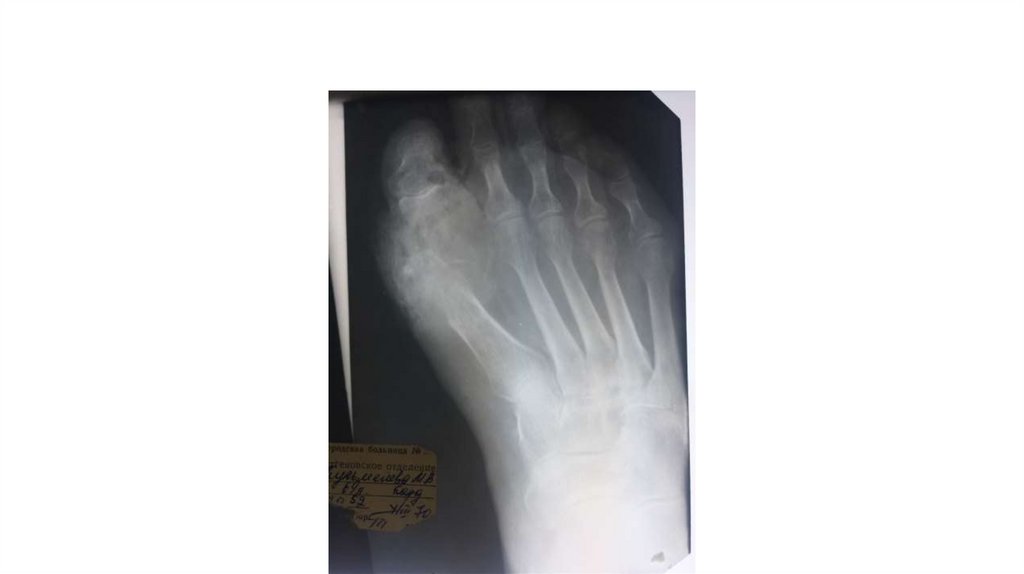

Воспалительные заболевания опорнодвигательного аппарата

«Воспалительные

заболевания опорнодвигательного аппарата»